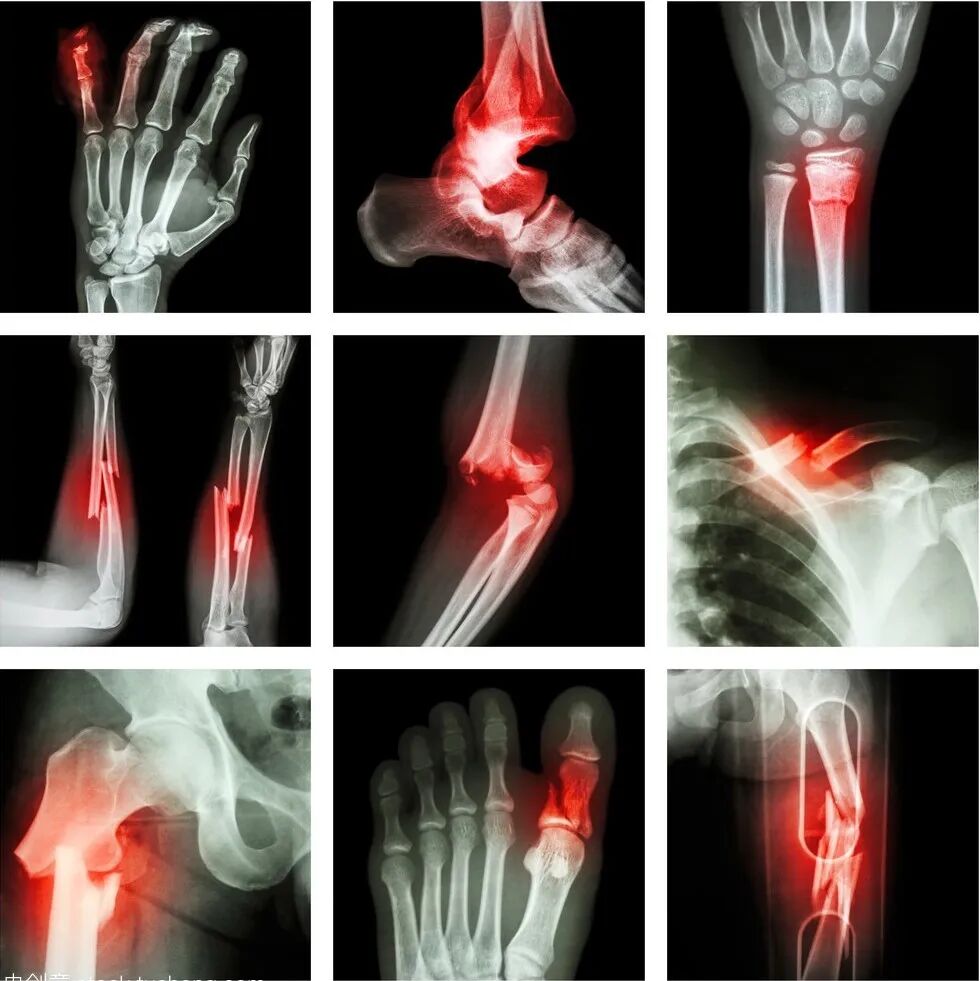

骨伤是地震中最易发生的伤害,该如何急救处理?

骨折如何判断

一看:骨折后,骨折部位肿痛,患侧移动不自然或是移动有困难,移动时会非常疼痛;与正常的一侧肢体不同;直接从伤口就可以看见断裂的骨头(即为开放性骨折)。

二摸:骨折部位变形,会出现异常形态。

三听:受伤时听到“啪”的裂声, 移动时有“嘎吱嘎吱”的摩擦声。